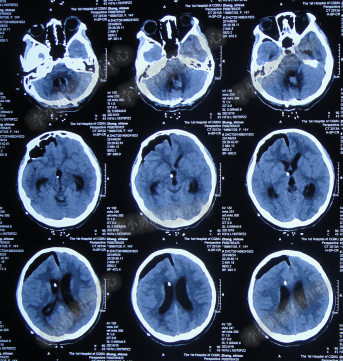

脑室外引流术后9天内,脑积水仍没有得到控制(图-12、图-13、图-14),且脑脊液仍有细菌。

图-12:2014年6月28日头部CT

图-13:2014年6月30日头部CT

图-14:2014年7月3日头部CT